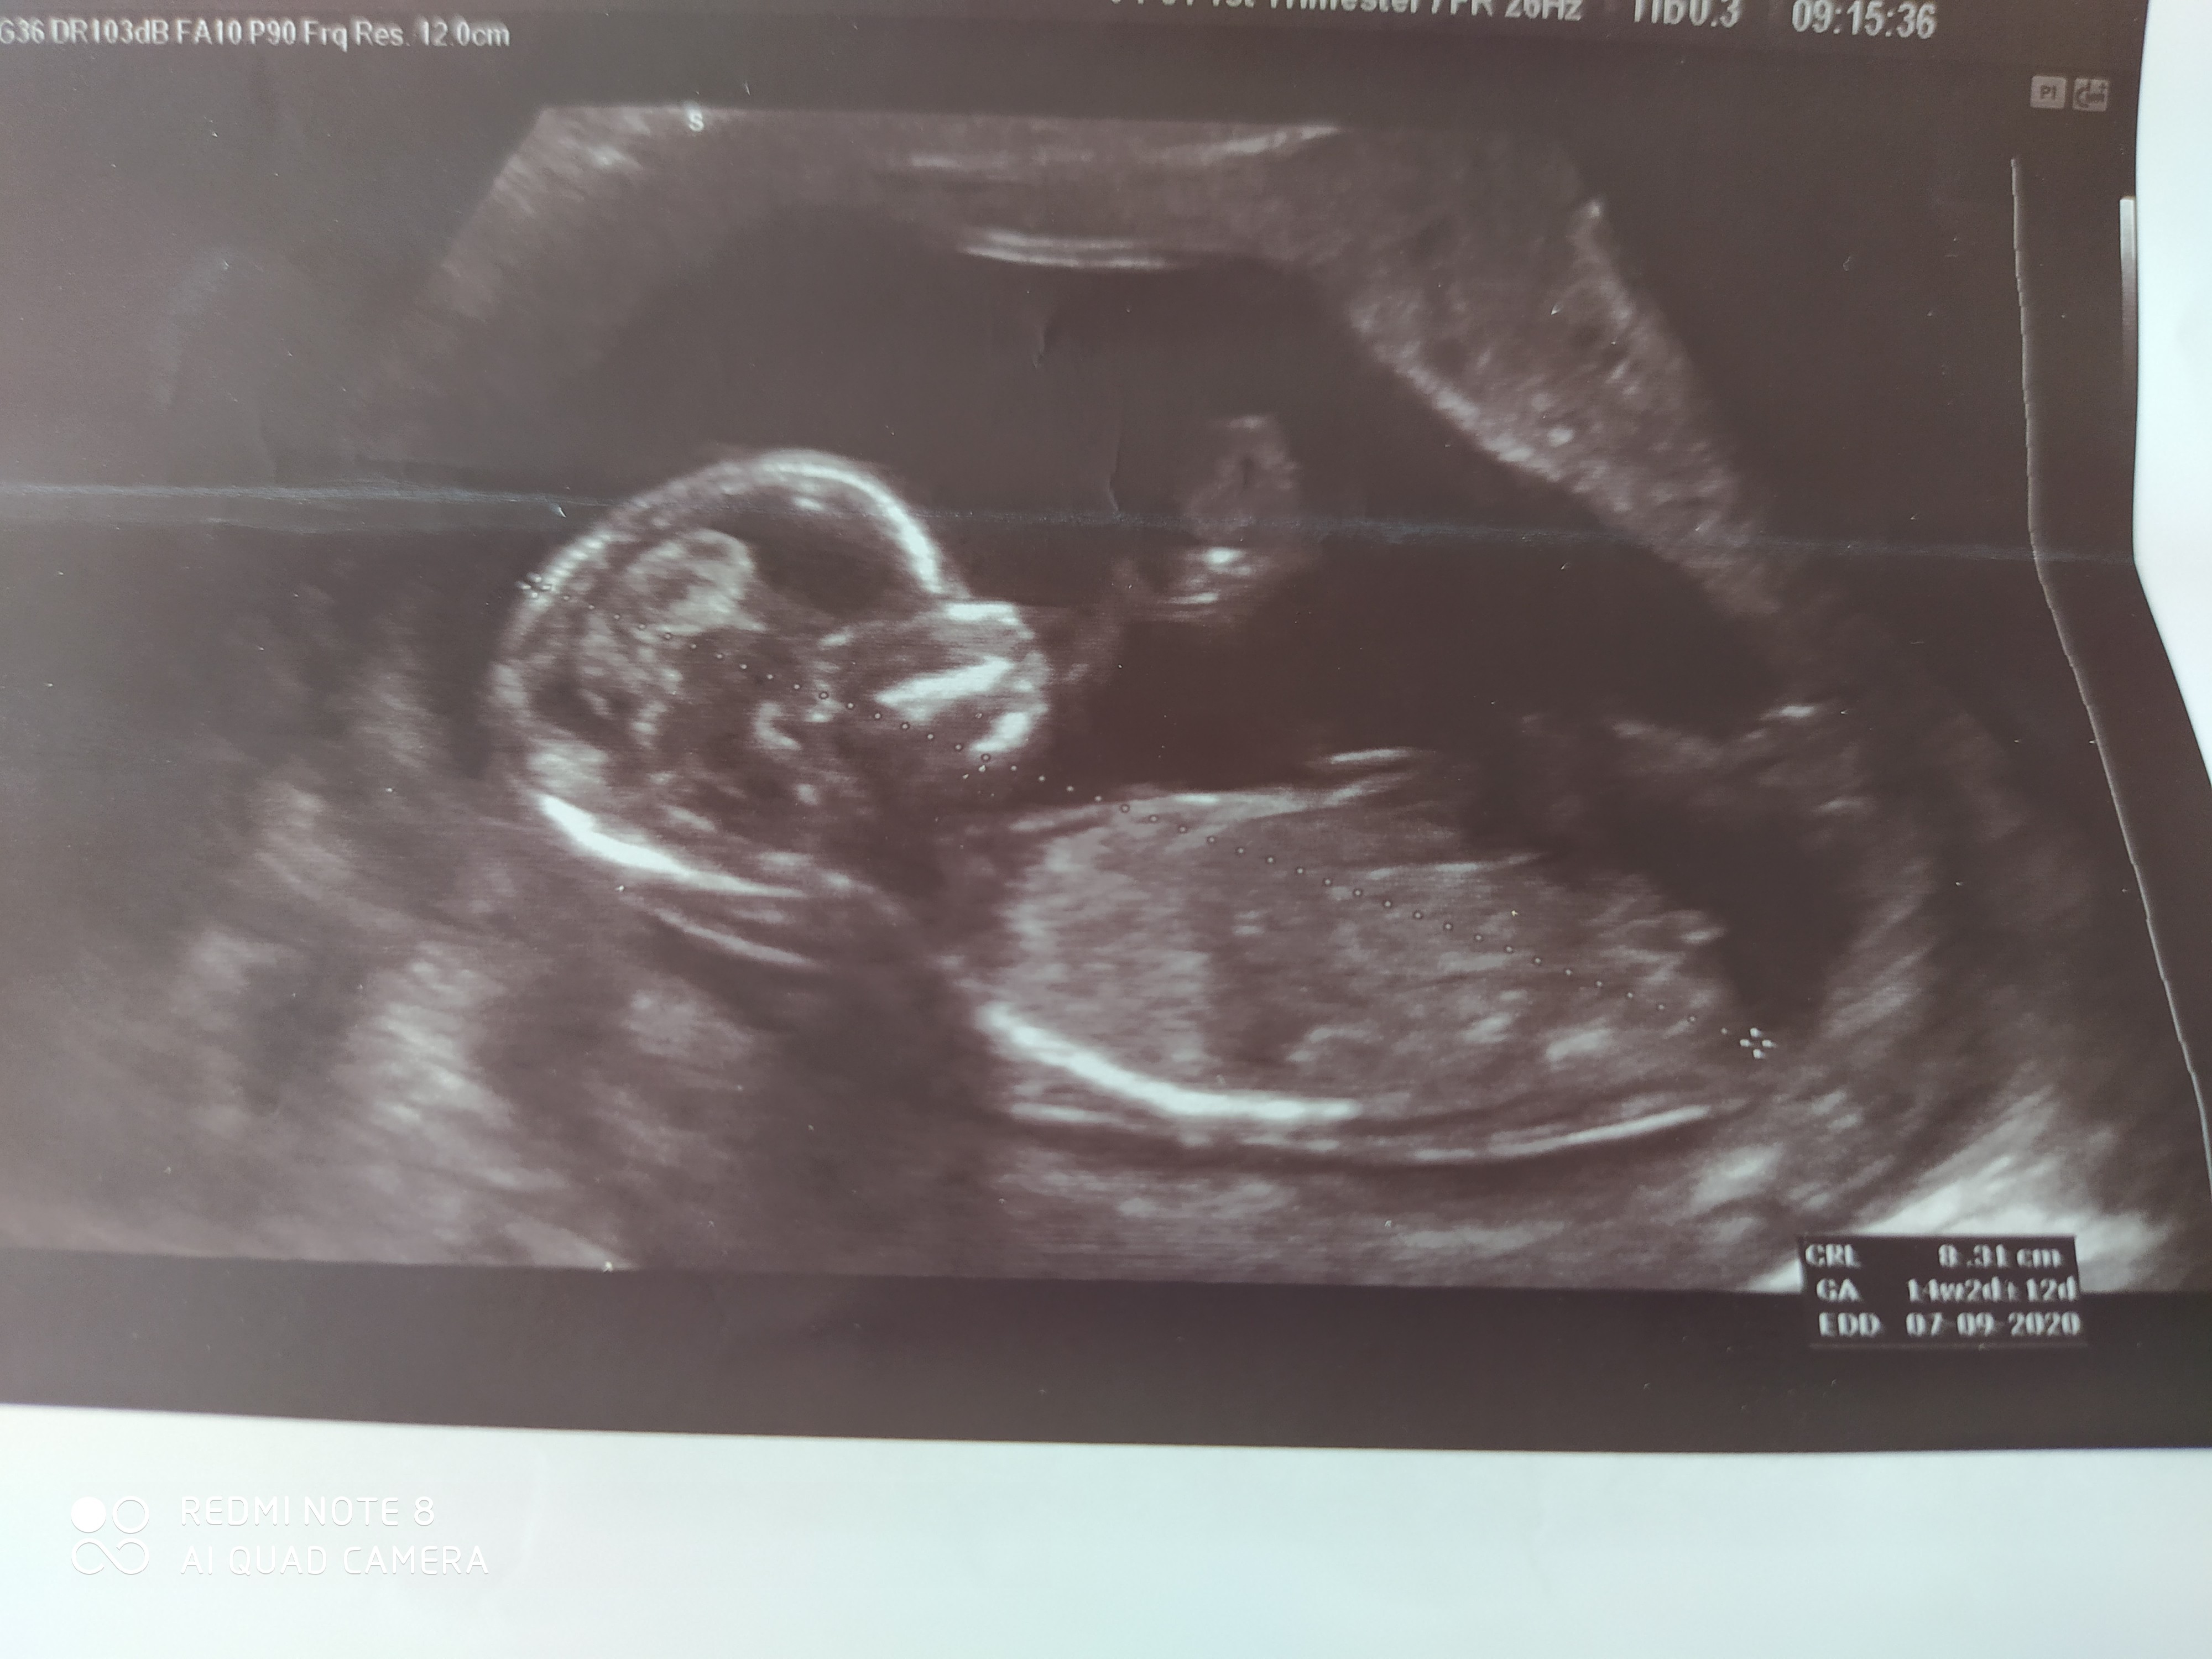

Witam serdecznie🙂 Byłam ostatnio na badaniach prenatalnych i dowiedziałam się, że będzie dziewczynka 14+2 TC ,a wcześniej w 13 TC byłam na zwykłym USG i lekarz obstawiał chłopca... może byście zerknęły na zdjęcia i dały znać kto mnie zamieszkuje..z góry bardzo dziękuję za pomoc i pozdrawiam 🙂

• IMG_20200313_081136.jpg

IMG_20200313_081136.jpg

1,2 MB · Wyświetleń: 245

• IMG_20200313_082844.jpg

IMG_20200313_082844.jpg

1,2 MB · Wyświetleń: 246

Dzoecko jest bokiem, nie da się nic zobaczyć 😉 ale skoro na prenatalnych tak powiedzieli, to bym się tego trzymała

Hmmm ginekolog na podstawie tych zdjęć stwierdzała 😉..na fb jest też taka strona nub gender i na podstawie tego odstającego wyrostka potrafią ocenić tylko, że ja nie bardzo się w tym orientuję 🙂

Przez ostatni tydzień już się oswajałam z wiadomością o chłopczyku,a teraz na prenatalnych ginekolog zaskoczyła nas tą dziewczynką, gdy jej wspomniałam, że tydzień wcześniej byl chłopiec to zaczęła wnikliwie oglądać, powiększać i stwierdziła, że nic nie odstaje i niby między nogami nie ma.. płeć nie jest dla nas najważniejsza, choć nie powiem, że nadzieja o dziewczynce bardzo nas ucieszyła, gdyż synka już mamy ☺️ pozdrawiam 😉

Hey @AśkaW89 :) choć z 14tc już się nie patrzy na nuba... (teraz jak będziesz po 16tc to niech robi potty shot i już będzie coś widać ;) ) to powiem Ci że mnie wyglada również na dziewczynkę